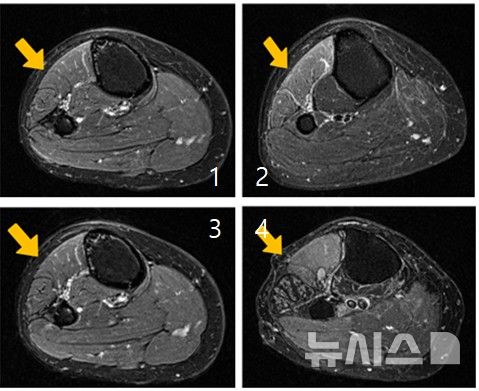

![[서울=뉴시스] 근육 손상이 진행되는 과정을 단계별로 보여주는 MRI 사진. (사진= 한림대춘천성심병원 제공)](https://img1.newsis.com/2026/03/27/NISI20260327_0002095430_web.jpg?rnd=20260327113636)

[서울=뉴시스] 근육 손상이 진행되는 과정을 단계별로 보여주는 MRI 사진. (사진= 한림대춘천성심병원 제공)